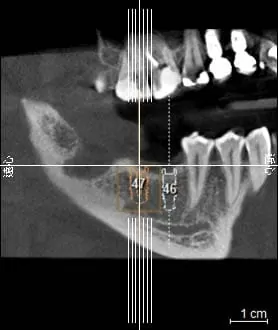

(圖2)橘色虛線為模擬放入植體的適當位置

對於植牙醫師而言,CT的便利性,即是具有模擬植體植入的功能(圖2)。因為每位患者的顎骨結構不同,為了因應病人口腔現況及符合牙齒對應的咬合功能,植牙醫師需考量在術前判斷植體植入的位置是否恰當,由於CT所拍攝出來的影像是立體的,可以360度旋轉(圖3),可進一步判斷齒槽骨的骨質及植體植入的寬度與深度以避免植牙常見的問題案例:上排植體穿過鼻腔造成鼻竇破裂或是下排植體不小心碰到齒槽骨神經,可能造成半邊臉麻痺等問題發生(圖4)。所以進行拍攝「口腔電腦斷層CT」也是對患者進行植牙手術的安全與保障。